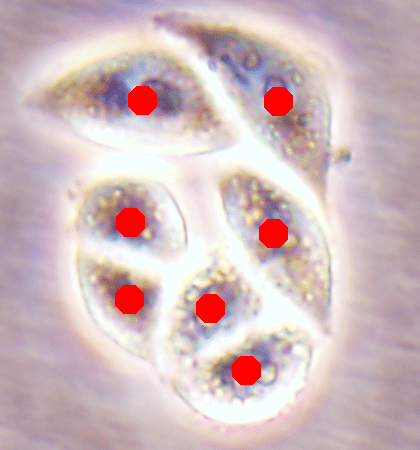

Since the main goal of this work is cell detection, our DeepDistance models define the estimation of an inner distance map as the main task and find regional maxima on this estimated map to detect cells. The motivation behind these choices is the fact that the inner distance definition gives sharp increases at cell centers and the locations with these sharp increases can be detected by finding regional maxima. Hence, to obtain accurate detections, one should estimate an inner distance map with distinct differences between the cell centers and their surrounding pixels such that these centers can be identified as regional maxima. That is, one should estimate a map consisting of sharp enough bright regions close to the cell centers. To improve the performance of the task of this inner distance estimation, our models take advantage of multi-task learning approach. This approach helps the models become more robust to avoid overfitting a task, compared to the approach of learning the same task alone with a single-task model (Caruana, 1997). To get more insight in this multi-task learning approach, this section visually analyzes the estimated maps of single-task and multi-task models.

![]() |

| (a) | (b) | (c) | (d) |

For the independent test samples given in Fig. 4, Fig. 6a shows the maps of the calculated inner distances when the ground truths are given. Figs. 6b, 6c, and 6d illustrate the inner distance maps estimated by the SingleInner method, the proposed DeepDistance model, and its extended version, respectively. SingleInner learns its map as a single-task whereas our models define auxiliary tasks and learn the inner distance map in parallel to these auxiliary tasks, forcing them to learn shared representations with a shared encoder path. The latter type of learning, which is an example of multi-task learning, is known to be effective for increasing the performance of individual tasks for many domains. We also observe this performance increase in the estimated maps given in Fig. 6. SingleInner cannot successfully detect the three cells shown inside red ellipses since it cannot produce sharp enough bright regions (with distinct enough estimated distances) for these cells. Although DeepDistance, which uses one auxiliary task, leads to brighter regions for these cells, they are still not sharp enough for two of them to be identified as regional maxima. The extended version of DeepDistance, which uses one more auxiliary task, does better job in inner distance estimations such that they have sharp enough bright regions for all of these three cells.

In this figure, it is worth to noting two points: First, all methods apply the h-maxima transform on their estimated maps beforehand to suppress noise, and hence, to prevent over-segmentations and false positives. If it was not applied, SingleInner might give regional maxima for some of the three cells even though the distances estimated for their centers were not that distinct (bright). However, that case would also give many over-segmented cells and false positives. Second, none of the methods identify the cell shown inside a blue ellipse although their estimated distances yield bright regions for this cell. It is due to the evaluation method, which matches an annotated marker and a detected cell based on the distance between them since a test set image does not have boundary annotations but just a dot on each cell. In our experiments, a distance threshold is set to 30, considering image resolutions and the average cell size. This threshold may give a few incorrect matchings especially for larger cells, (e.g., the cell shown inside the blue ellipse). Increasing this threshold solves the problem for this particular cell, but this time, it will result in many incorrect matchings of detected cells with distant markers (or vice versa).